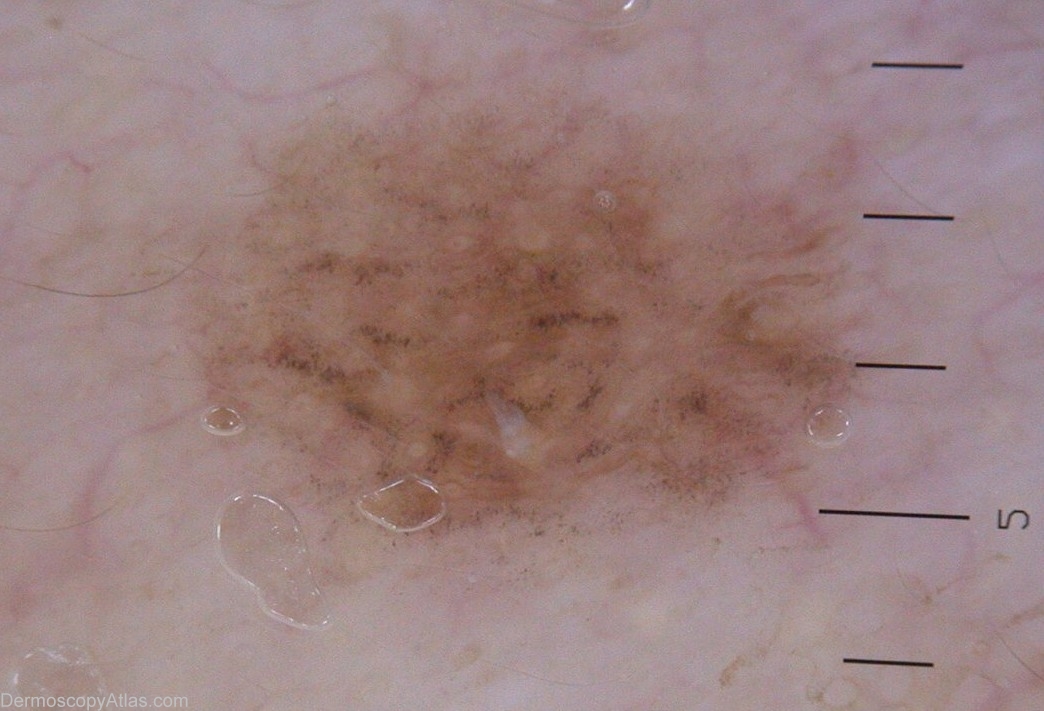

Diagnosis: Lentigo Maligna

Type: Heine

History: This lady came for the removal of dark spots on her face. Most of them were solar lentigos. One one them, right eyelid, had a suspect dermoscopic image. Excision followed by pathology revealed a small lentigo maligna.

Keywords: slate-grey dots, annular-granular structures, rhomboidal pseudo-network